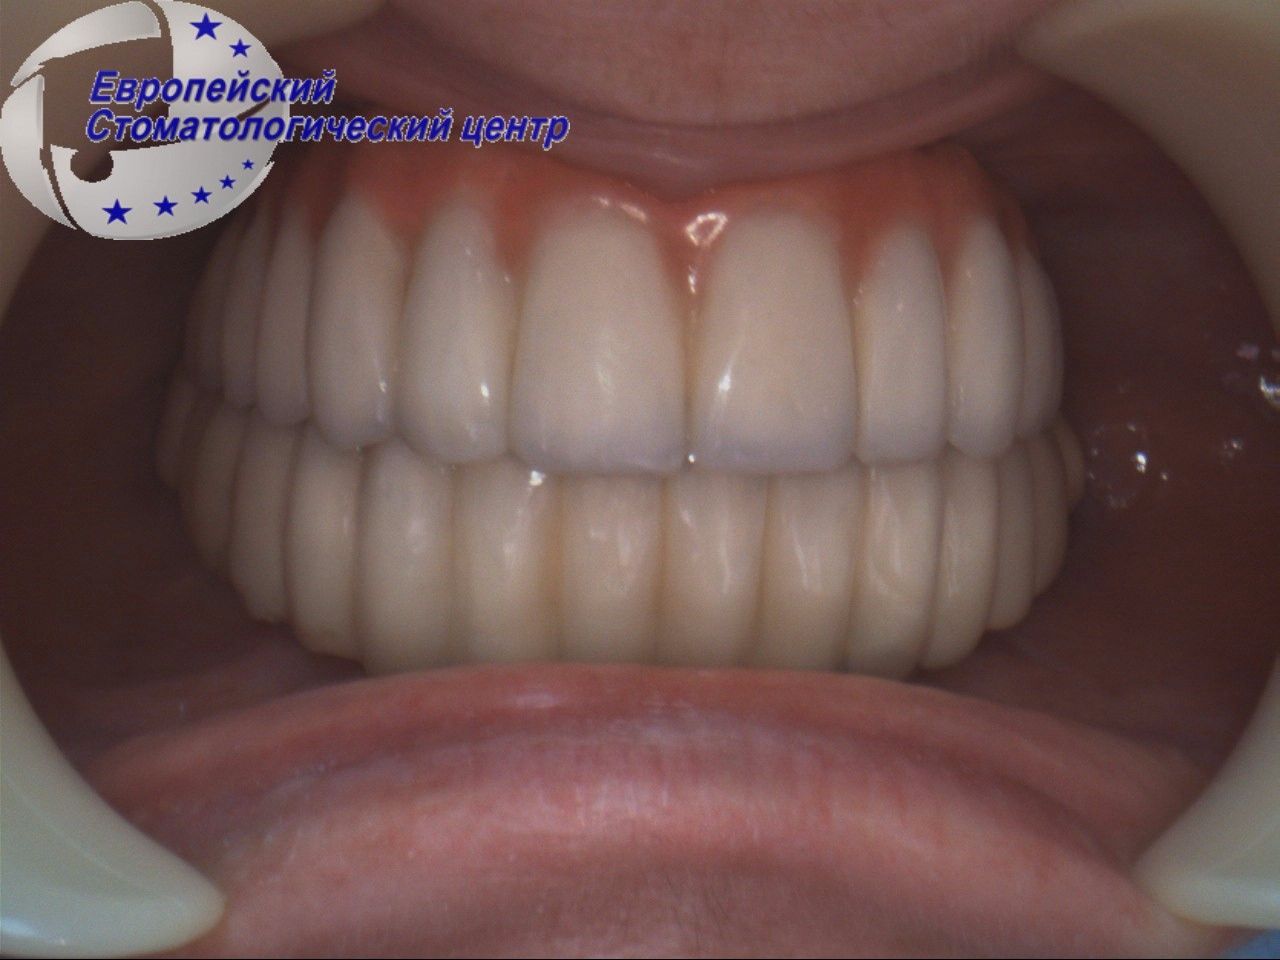

After 4 months, permanent crowns were installed on the zirconia frame (see pic. 6-8).

Picture 6

Picture 7

Picture 8